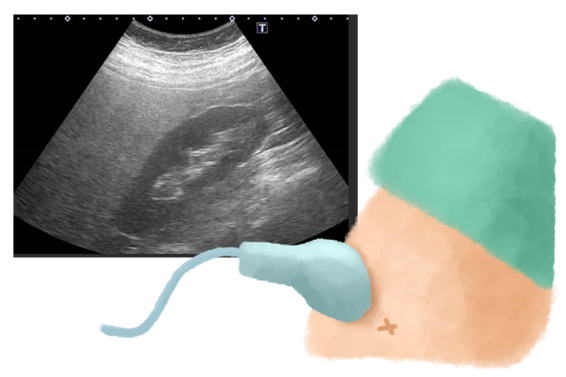

腹部超音波(エコー)検査

脂肪が溜まった肝臓は、超音波で白っぽく輝いて見えます(「ブライトリバー」と呼ばれます)。肝臓の形や、肝がんの発生がないかも確認できる、基本かつ非常に重要な検査です。